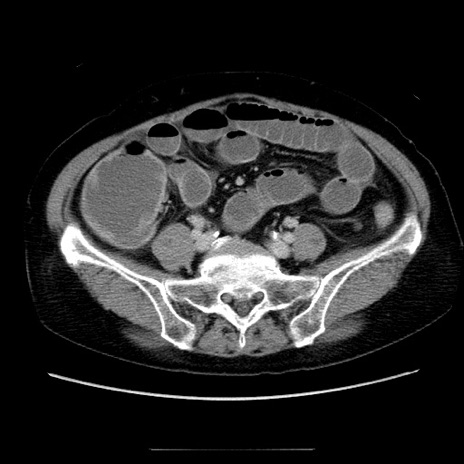

冠状断像

【症例】70歳代女性

【主訴】お腹が張る

【現病歴】1週間くらい前から腹部膨満の自覚あり。昨日夜から増悪したため、本日救急外来受診。

【身体所見】意識清明、BT 36.5℃、BP 165/106mmHg、HR 80bpm、SpO2 98%、腹部:膨満、軟、自発痛・圧痛なし、触診にて不快感あり、腸蠕動音:減弱

【データ】WBC 12600、CRP 1.04